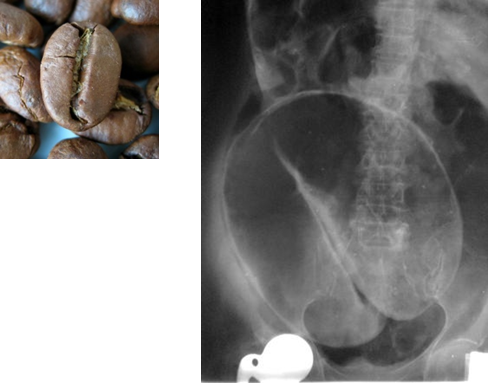

Sigmoid Volvulus

Radiological Appearance:

Coffee bean sign